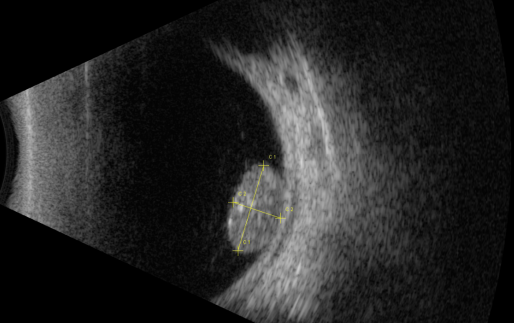

視網(wǎng)膜母細(xì)胞瘤的分類和治療

視網(wǎng)膜母細(xì)胞瘤是嬰幼兒常見的眼內(nèi)惡性腫瘤,可危害患者的視力、眼球和生命。其惡性程度高,多發(fā)于兒童,尤其是3歲以下的兒童,常表現(xiàn)為白瞳癥,可侵及單眼或雙眼。

根據(jù)腫瘤的表現(xiàn)和發(fā)展過(guò)程可分為眼內(nèi)期、青光眼期、眼外期和全身轉(zhuǎn)移期。

開始在眼內(nèi)生長(zhǎng)時(shí)外眼正常,因患兒年齡小,不能自述有無(wú)視力障礙,因此本病早期一般不易被家長(zhǎng)發(fā)現(xiàn)。當(dāng)腫瘤增殖突入玻璃體或接近晶體時(shí),瞳孔區(qū)出現(xiàn)黃白色反光,如貓眼樣(“黑貓眼”),此時(shí)常因視力障礙而瞳孔散大、白瞳癥或斜視被家長(zhǎng)發(fā)現(xiàn)。